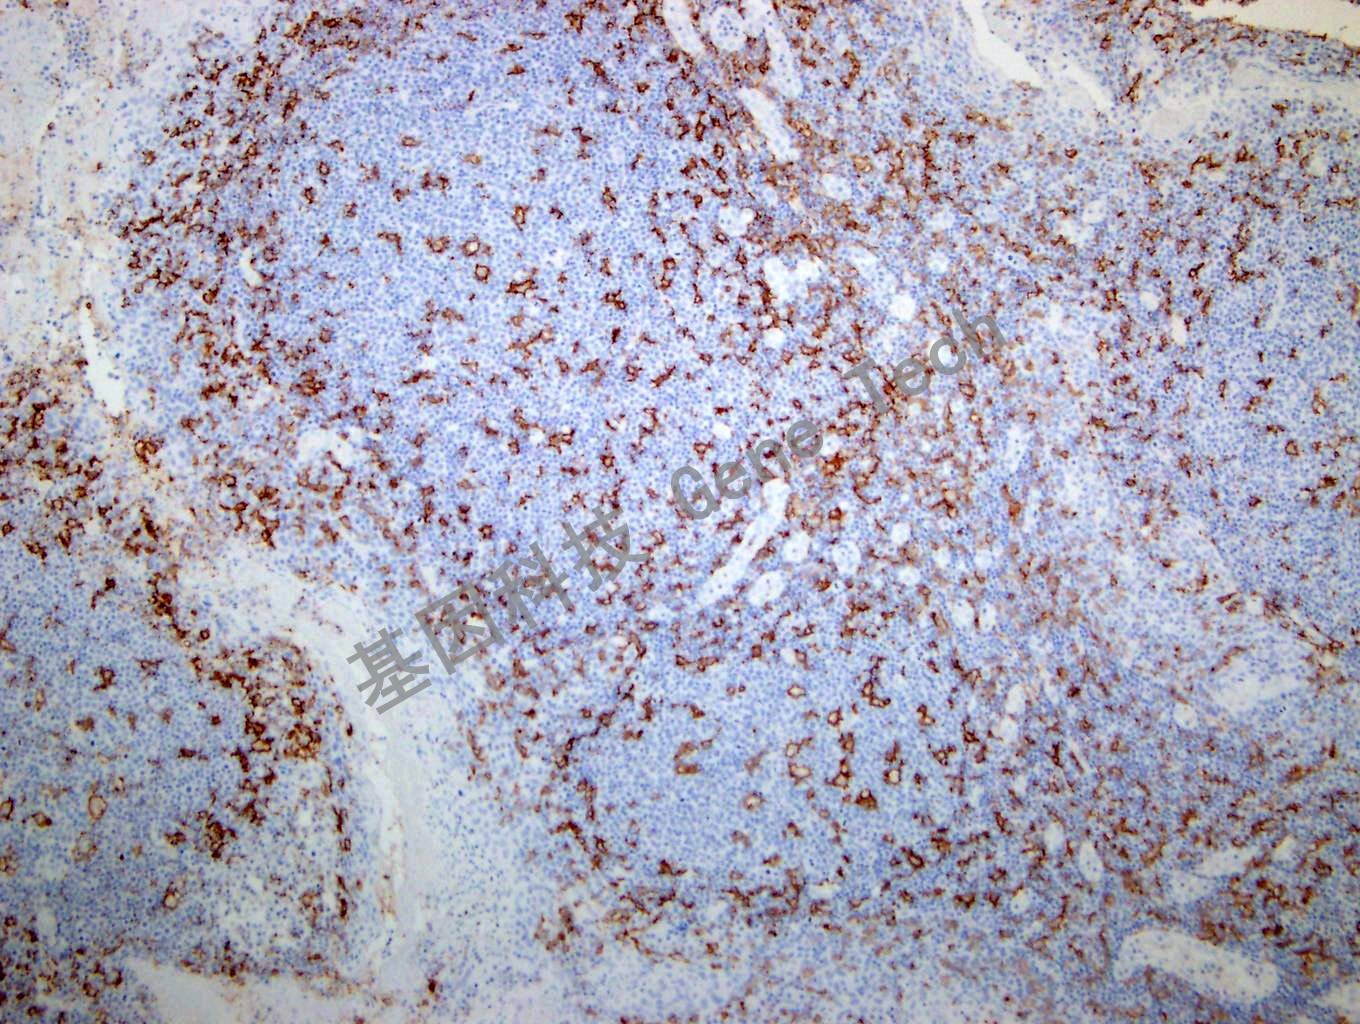

| 克隆號:5D11 | 陽性對照:扁桃體 | 陽性部位:細胞膜 |

| 預(yù)處理:高pH熱修復(fù) | 適用:石蠟切片/冰凍切片 | 顯色系統(tǒng):GTvisionTM |

| 簡介:CD11c 是一種I 型跨膜蛋白,屬于整合素α 鏈蛋白家族,又稱IGTAX。可與整合素β2 形成異源二聚體,是白細胞特異的整合素組成形式。同時該二聚體還是非激活補體C3b 的受體4CR4),參與粒單核細胞與活化的內(nèi)皮細胞粘附過程,參與補體包被顆粒物被吞噬清除過程。CD11c 在人體大多數(shù)樹突狀細胞中有高表達,此外在單核細胞、中性粒細胞、巨噬細胞及部分B 細胞中也會有表達。在毛細胞白血病、急性非淋巴細胞白血病和某些B 細胞來源的慢性淋巴細胞把血病中有表達。CD11c 推薦作為抗體組合的一部分,有助于血液系統(tǒng)惡性腫瘤的診斷以及組織內(nèi)巨噬細胞 / 樹突狀細胞的鑒別。 | ||

| 扁桃體石蠟切片,用 CD11c(GT2270)染色,細胞膜陽性,DAB 顯色。(10×) | ||